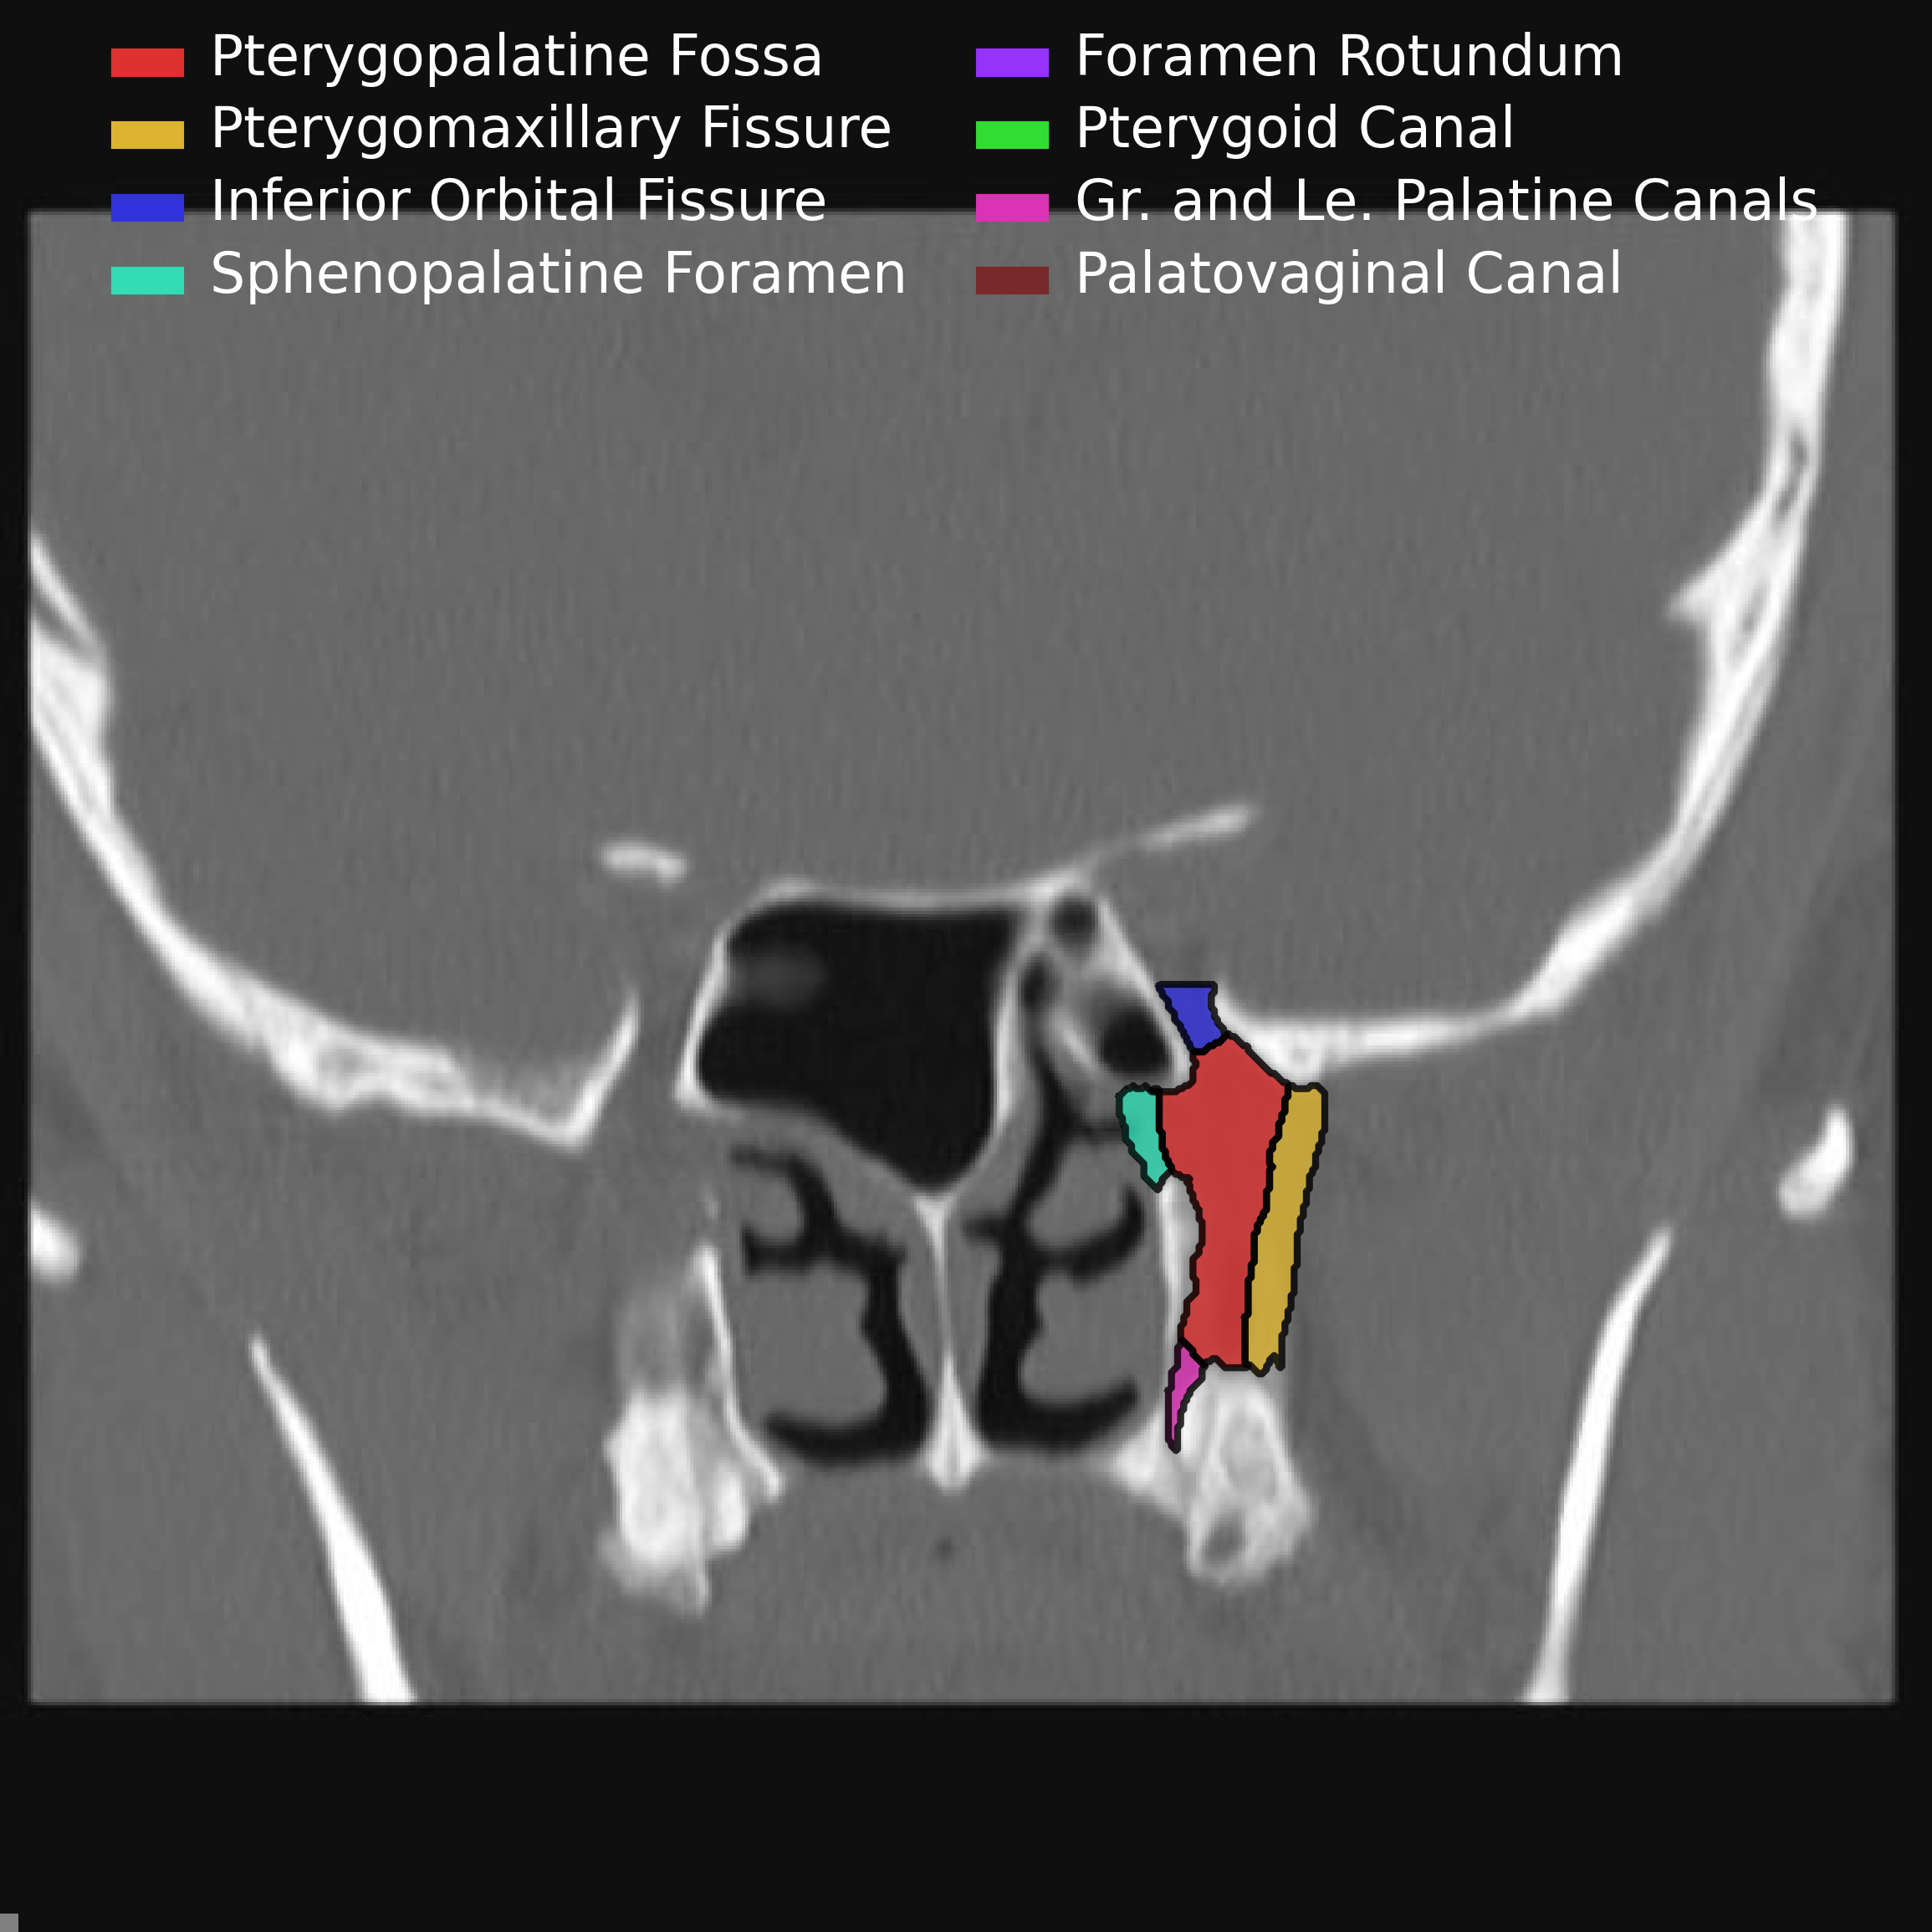

The following pictures are a fantastic way to visualize the borders rather than just memorizing them which is a sure fire way to forget them by tomorrow.

• Anterior & Superior - communicates with inferior orbital fissure

• Inferior - Greater & lesser palatine canals

• Communicates with palate

• Lateral - Pterygomaxillary fissure

• Communicates with masticator space

• Medial communication - Sphenopalatine foramen & Palatine bone

• Communicates with nasal cavity

• Transmits

• Sphenopalatine artery

• Posterior superior nasal nerves & nasopalatine nerve

• Posterior

• Posterior-medial - Palatovaginal canal

• Communicates with nasopharynx

• Transmits pharyngeal nerve and pharyngeal branch of maxillary artery

• Posterior-superior - Foramen rotundum

• communicates with Meckel cave & Cavernous sinus

• Posterior-inferior - pterygoid canal (aka vidian canal)

• Communicates with middle cranial fossa

• Transmits vidian nerve, artery and vein